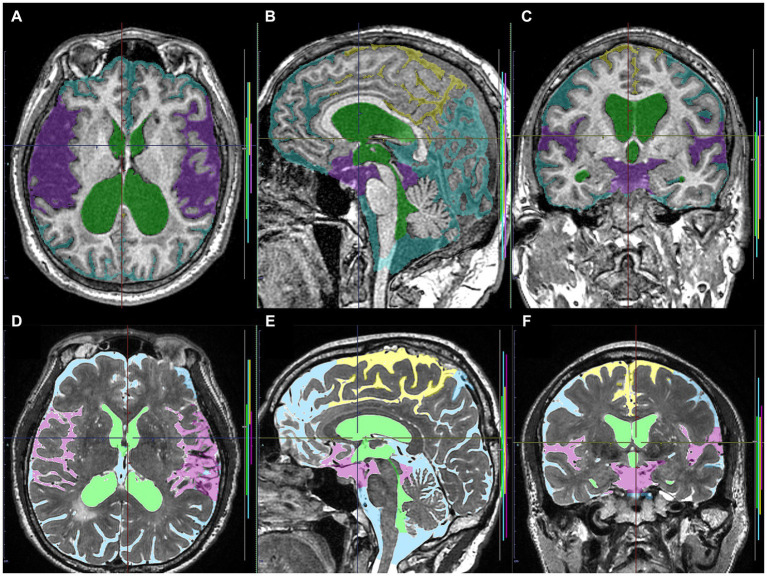

As ground truth labels in our AI models, input image masks for volumetric semantic segmentation on the 3D T1-weighted MRI were created by combining manual segmentation with the 3D Viewer and fully automatic segmentation with the Brain Subregion Analysis applications (Figures 1A–C) on an independent 3D volume analyzer workstation (SYNAPSE 3D; FUJIFILM Corporation, Tokyo, Japan). In the Brain Subregion Analysis application, intracranial spaces were segmented fully automatically into 26 subregions including ventricles and SAS within 1 min (ref. Yamada et al., 2023c). The input image masks from 3D T2-weighted MRI were also created using our original method, combining a simple threshold algorithm and manual segmentation (Figures 1D–F), as previously reported (ref. Yamada et al., 2015, ref. 2016a,ref. b). Total SAS were further segmented into the Sylvian fissure and basal cistern, and the high-convexity SAS, which was defined as the location above the body of the lateral ventricles, with the lateral end 3 cm from the midline, the posterior end in the bilateral posterior parts of the callosomarginal sulci, and the anterior end on the coronal plane perpendicular to the AC–PC line passing through the front edge of the genu of the corpus callosum (Figure 2; Supplementary Videos S1–S4) (ref. Yamada et al., 2023a). All input image masks as the ground truth labels were transferred to the SYNAPSE Creative Space for cloud-based AI development service (FUJIFILM Corporation). All masks were processed and formatted into a form that could utilize the training or inference process. Regarding the output of the inference process, feature maps were obtained. Overall, 159 T1-weighted images were assigned to 110 images for training, 30 for internal and 19 for external validation (test), and 180 T2-weighted images were assigned to 130 images for training, 30 for internal validation and 20 for external validation. Inference was performed in the images for internal validation and external validation.